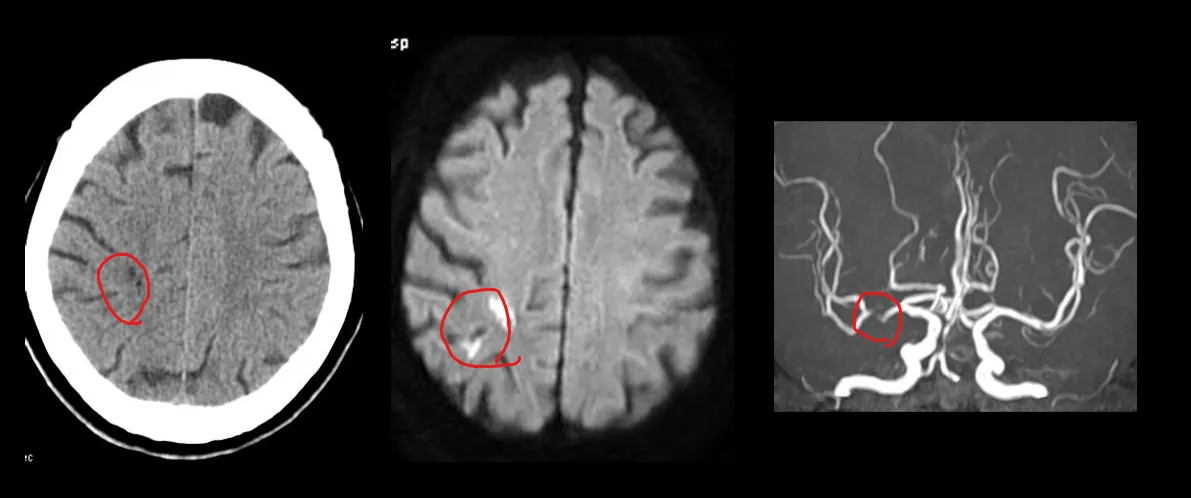

F5. 다 보고 아무 lesion이 없는 것 같으면 혈관을 봐라 (MCA나, Superior saggital sinus같은)

갑자기 우측 상지 마비가 발생하고 의식이 떨어진 환자. superior saggital sinus가 HU 80정도로 밝게 보인다. angio에서 이 병변은 thrombus로 확인되었다.

우측 centrum semiovale에 hypodense한 병변이 보이며, MRI에서 Rt MCA stenosis 가 관찰되었다.

좌측 centrum semiovale에 infarction이 보인다. MRI에서 동측의 ICA occlusion 이 발견되었다.